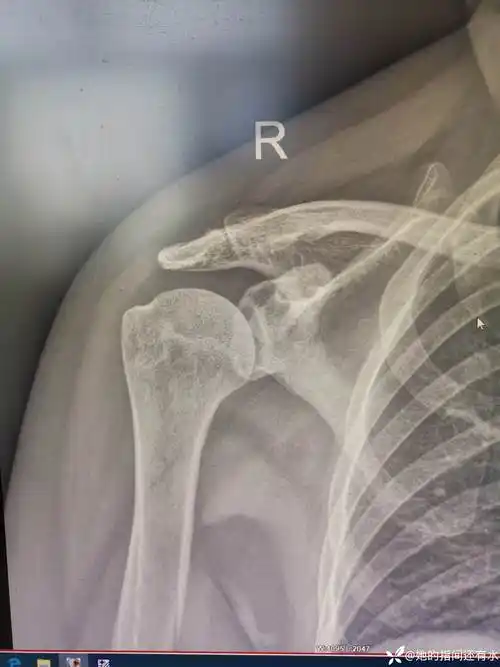

难复性肩关节脱位.患者肩关节处于脱位状态2个月 - 抖音

肩痛要及时就诊--陈旧性肩关节脱位病例